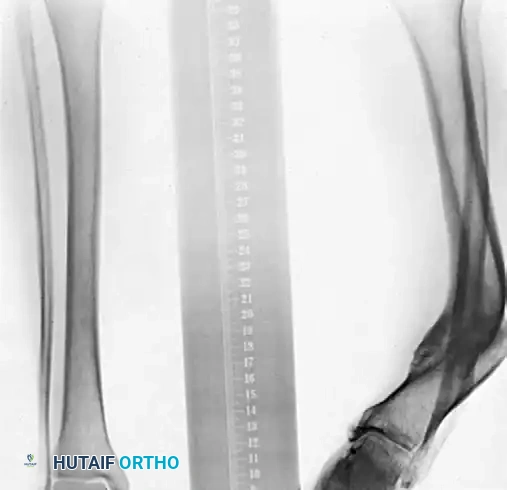

Image

Preoperative AP and Lateral radiographs demonstrating a severe varus malunion of the distal tibia.

Intraoperative radiograph showing the osteotomy of the tibia and fibula, with the anatomical reduction maintained rigidly by a circular external fixator.